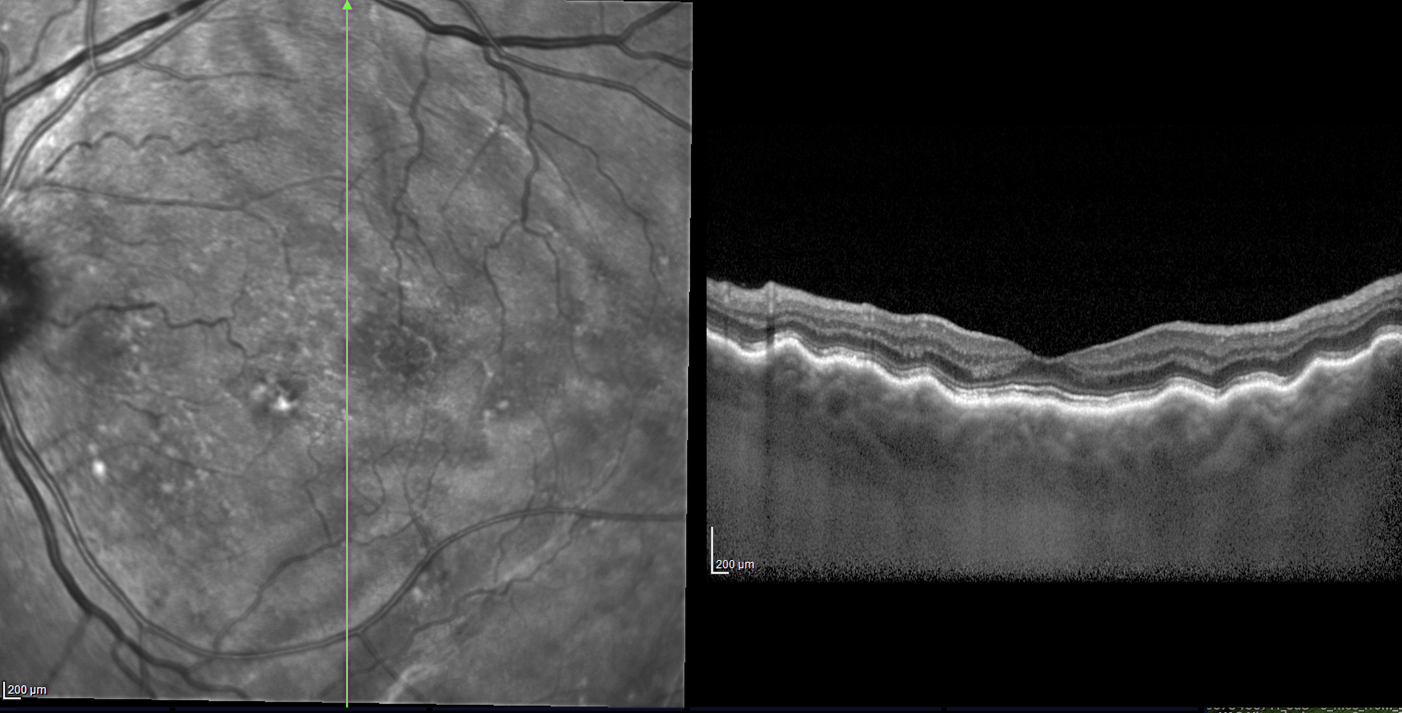

This OCT shows a retinal finding associated w/ thyroid eye disease.

What are choroidal folds?